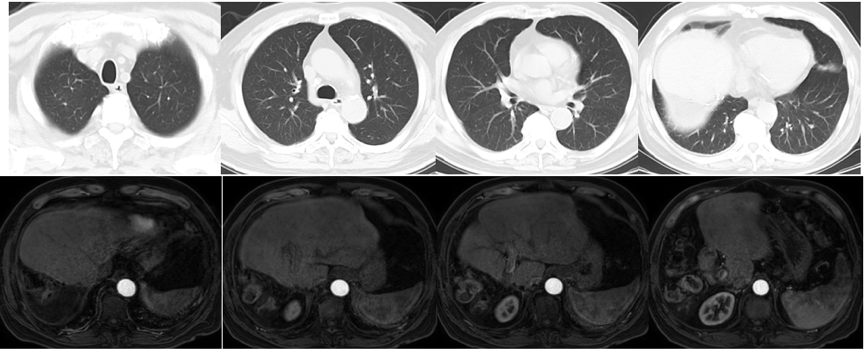

2021年3月8日复查AFP为>1210ng/ml;2021年3月8日复查CT提示,双肺转移双侧肾上腺转移;左侧肾上腺较前变小,但右侧肾上腺明显增大;右侧髂骨转移(图5)。

图5.2021年3月8日复查CT

2021年4月29日、2021年6月11日、2021年7月2日、2021年8月16日和2021年9月6日复查AFP分别为242ng/ml、11.93ng/ml、16.62ng/ml、52.61ng/ml和142.1ng/ml。2021年9月7日复查CT示,肺部病灶基本消失,双侧肾上腺病灶明显缩小(图7)。

图7.2021年9月7日复查CT